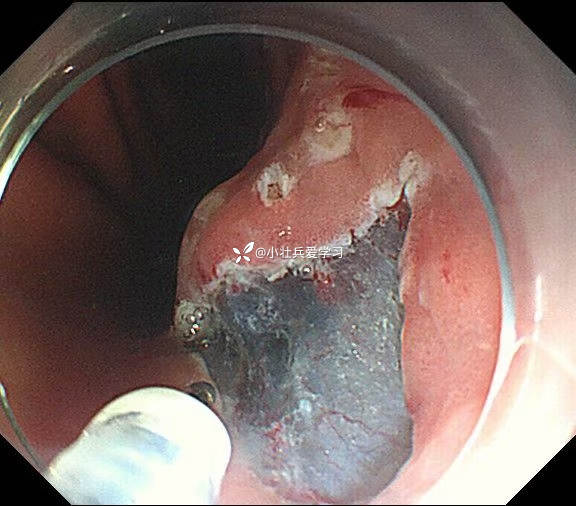

临床诊断:溃疡型胃角早癌

术前谈话诊断性ESD

术后病理示粘膜内癌(M3期),切缘阴性,达到治愈性切除标准,术后不用再追加外科手术、放化疗,对病人来说是不幸中的万幸。